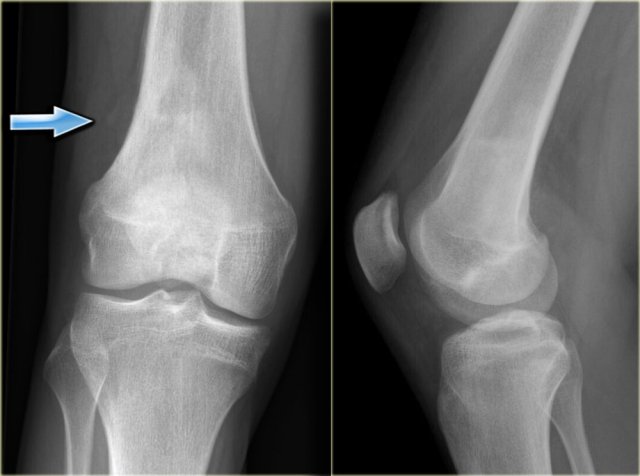

The image shows a calcified lesion in the proximal tibia without suspicious features.

This could very well be an enchondroma.

There were other features that favored the diagnosis of a low-grade chondrosarcoma like a positive bone scan and endosteal scalloping of the cortical bone on an MRI (not shown).

A chondrosarcoma was diagnosed at biopsy.